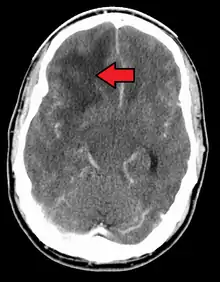

![]() | |

| Coronal MRI with contrast of a glioblastoma in a 15-year-old male | |

When viewed with MRI, glioblastomas often appear as ring-enhancing lesions. The appearance is not specific, however, as other lesions such as abscess, metastasis, tumefactive multiple sclerosis, and other entities may have a similar appearance.[58] Definitive diagnosis of a suspected GBM on CT or MRI requires a stereotactic biopsy or a craniotomy with tumor resection and pathologic confirmation. Because the tumor grade is based upon the most malignant portion of the tumor, biopsy or subtotal tumor resection can result in undergrading of the lesion. Imaging of tumor blood flow using perfusion MRI and measuring tumor metabolite concentration with MR spectroscopy may add diagnostic value to standard MRI in select cases by showing increased relative cerebral blood volume and increased choline peak, respectively, but pathology remains the gold standard for diagnosis and molecular characterization.